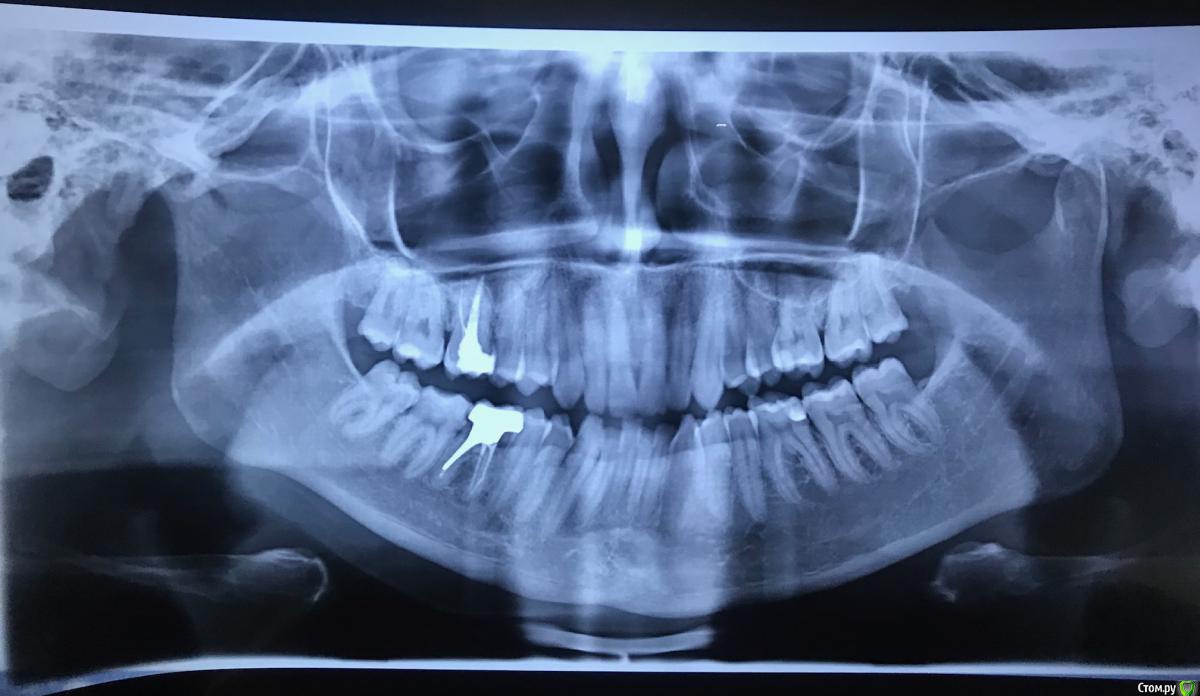

08.08 пришла на прием к стоматологу-терапевту. При осмотре полости рта (ни опухоли, ни покраснений), постукивании зубов (боли нет), ощупывании лимфоузлов (безболезненны и не увеличены) и анализе жалоб высказано предположение, что это боли от сустава. Сделана ортопантомограмма, снимок прилагаю. Заключение рентгенолога прилагаю, из найденного - 46 - апикальная гранулёма у медиального корня размером до 0,3 - 0,2 см. Но по словам стоматолога она таких болей дать не может.

09.08 проведен осмотр у стоматолога-хирурга. По снимку и по осмотру дан совет эту гранулёму пока не трогать, а за ней наблюдать. По поводу ощущений было сказано, что может быть много причин, ну да, может и сустав. Дан совет - если будет сильная пульсирующая боль и повышение температуры - пить антибиотик.